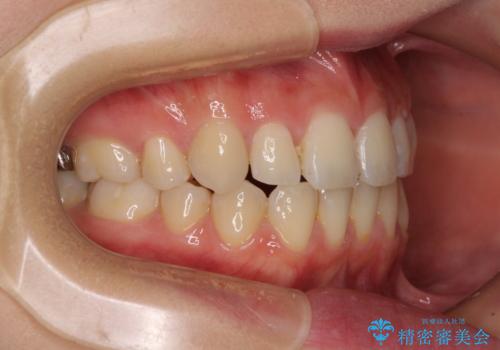

- 前歯のデコボコを気にして来院された患者様です。

本人は気づいていませんでしたが、下顎前歯が2本欠損しており、上下の歯列がアンバランスとなりデコボコになっていました。

上下のバランスを取るため、上顎左右第一小臼歯2本を抜歯し、ワイヤー矯正を行うこととしました。